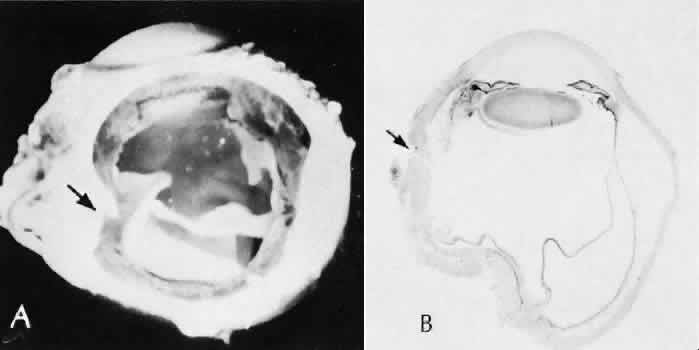

Retinal detachment (Fig. 42) occurs in approximately 2% to 8% of intracapsular cataract surgeries, compared with approximately 0.0013% in the general population. The incidence of retinal detachment after extracapsular cataract extraction and posterior chamber lens implantation ranges between 0.6% and 1.5%.121 Vitreous loss increases the incidence of postoperative detachments, particularly if there is vitreous incarceration into the cataract wound. The character of the retinal detachment is independent of the type of cataract surgery or the type of intraocular lens implanted. However, a lower incidence of proliferative vitreoretinopathy appears in cases of extracapsular cataract extraction than was formerly seen with intracapsular cataract extraction.

Fig. 42. Two cases of retinal detachment following cataract extraction. A. Retinal detachment was identified 4 weeks after cataract extraction. Fixed retinal folds indicate that the situation is inoperable, so no surgical repair was attempted. The anterior chamber angle has become occluded because of neovascularization associated with ischemic retina. B. Retinal detachment was identified 5 weeks after cataract extraction. Two attempts at surgical repair failed. The large equatorial cystic spaces indicated the presence of a scleral-buckling element. The actual material of the sponge and buckle has been lost during tissue processing. The cystic nature of the detached retinal tissue indicates that there was an extended time between the last retinal reattachment attempt and enucleation. In this case, peripheral anterior synechiae are present. The indication for enucleation was most likely a blind painful eye due to secondary glaucoma and reactive uveitis. (Hematoxylin-eosin stain; × 3.)